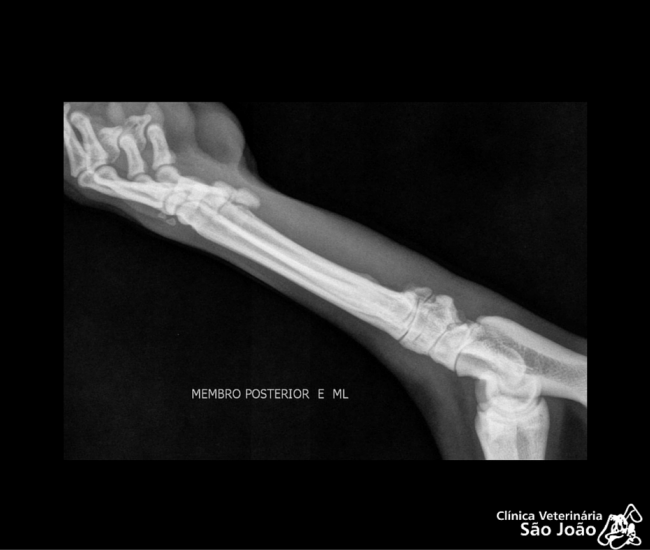

- Diferentemente do raio-x analógico, este raio-x oferece altíssima definição e todas as vantagens da tecnologia digital. É possível aproximar a imagem, trabalhar o contraste, exposição.O software permite ainda avaliações da medida cardíaca do animal e graus de displasia coxofemoral, por exemplo – explica o Dr. Nardeli Lucena.

- melhor qualidade da imagem;

- melhor detalhamento técnico;

- diagnósticos mais precisos;

- sofware com medidas para avaliações do tamanho cardíaco e medições dos ângulos de Norberg para diagnóstico e classificação de displasias coxofemorais;